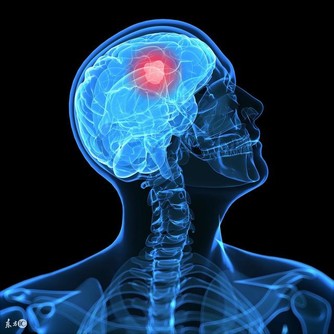

大腦跟人體任何部位一樣,運作機能會隨著時間的流失而慢慢衰退。

22歲以後,大腦中的神經細胞會慢慢減少。

等到40歲之後,人體新陳代謝逐漸變緩,

大腦細胞的功能也跟著減退,從而對記憶力和大腦功能造成影響。

雖然大腦的衰老不可避免,但通過一些手段和方法卻能減緩它的衰老速度。